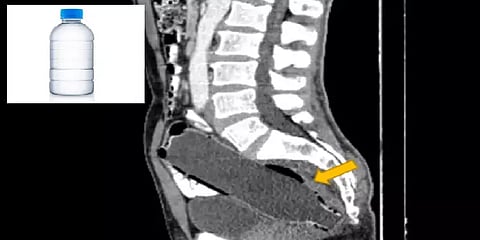

இது தொடர்பாக Journal Clinical Case வெளியிட்டுள்ள அறிக்கைப்படி, 50 வயது கொண்ட அந்த நபர் 19 சென்டிமீட்டர் அளவு கொண்ட தண்ணீர் பாட்டிலின் மேல் பகுதியை இழுத்தால் வெளியே எடுத்துவிடலாம் என எண்ணி அதன் அடிப்பகுதியை தன்னுடைய ஆசன வாய் வழியாக உள்ளே நுழைத்திருக்கிறார்.

அதன் பிறகுதான் மனைவி அவரை மருத்துவமனைக்கு அழைத்துச் சென்றிருக்கிறார். அங்கும் முதலில் கூறாமல் இருந்த அவரின் செயல் CT ஸ்கேன் எடுத்த பிறகு அவரது குடலில் பாட்டில் இருந்தது கண்டறியப்பட்டிருக்கிறது.